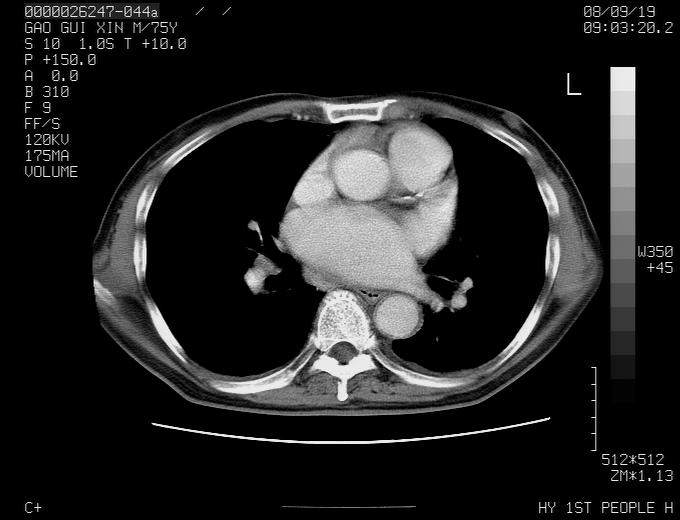

感谢各位老师的意见,左上肺病灶,我本人趋向结核,原因:左上肺见两个类圆形结节,仔细回顾4月份ct似乎原片在该处有条片状密度增高影,强化不明显。

现上传增强片,请各位老师仔细帮我看一下。

右上肺可见条索状影,并可见钙化,左上肺结节可以考虑为结核球,但气管前腔静脉后有肿大淋巴结,本人觉得左上肺结节不能排除转移瘤的可能,右上肺为陈旧性结核灶。

左肺上叶周围性肺癌并纵隔多组lnm.不可能是tb.

左肺上叶尖段瘢痕癌并纵隔淋巴结转移解释更好一些.

别再ct讨论了,一个纤支镜检查马上明确.肺癌不会错的!应该是低分化鳞癌.

1)左肺上叶尖段周围型肺癌并纵隔淋巴结转移。2)冠状动脉及主动脉钙化。